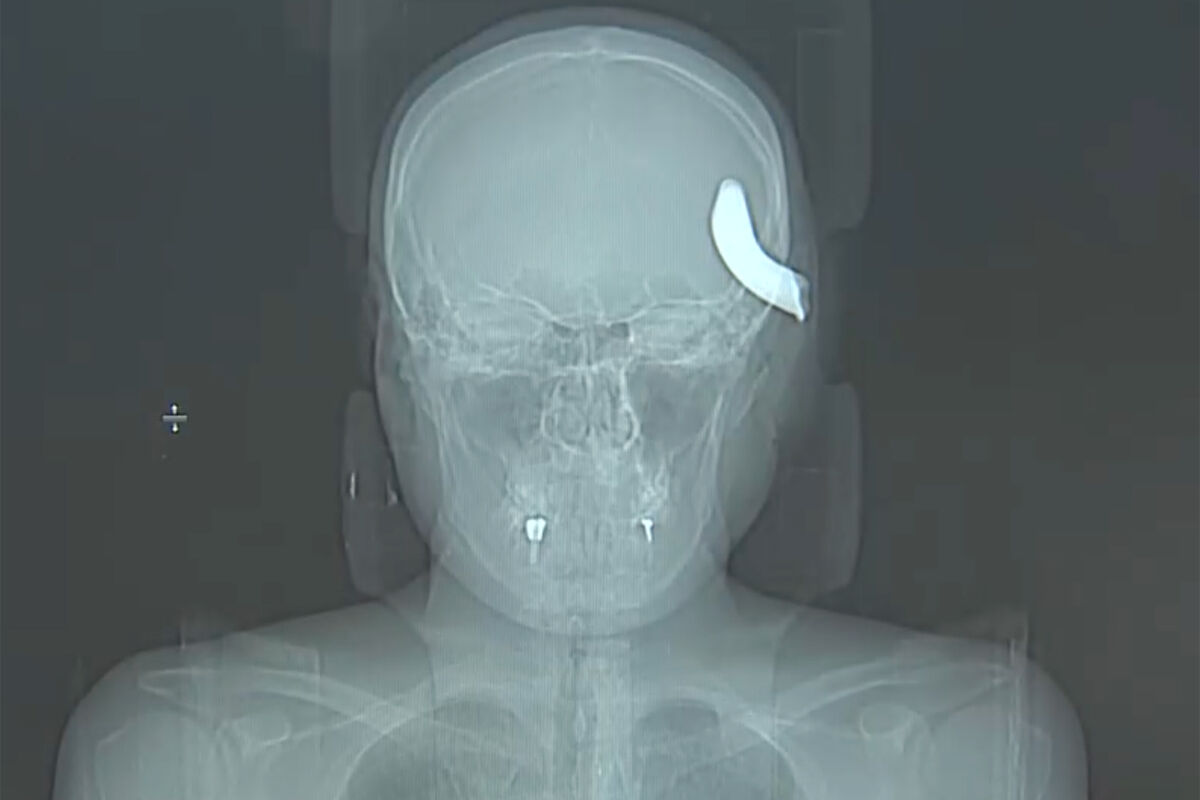

В Санкт-Петербурге врачи Елизаветинской городской больницы спасли 34-летнего мужчину, которому в голову вошел металлический крюк. Об этом врачи больницы рассказали в беседе с журналистами телеканала «Санкт-Петербург».

Инцидент, в результате которого пострадал мужчина, произошел в апреле. Петербуржец помогал другу с машиной, которую тянули на тросе, когда часть сломавшегося крюка отлетела ему в голову. В медицинское учреждение пострадавшего доставили в тяжелом состоянии.

На извлечение фрагмента крюка врачи потратили три часа. В процессе операции пациенту удалили часть костной ткани.